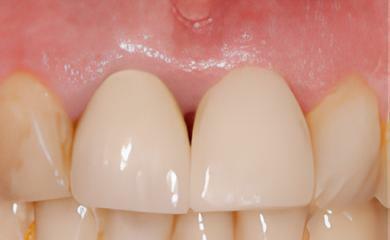

La couronne provisoire est confectionnée grâce à une empreinte immédiatement après l'extraction-implantation

Le PRF a permis une bonne cicatrisation des tissus osseux et gingivaux. La couronne provisoire ne doit pas "travailler" avec les dents du bas. La couronne d'usage en céramique sera conctionnée dans 4 à 5 mois.